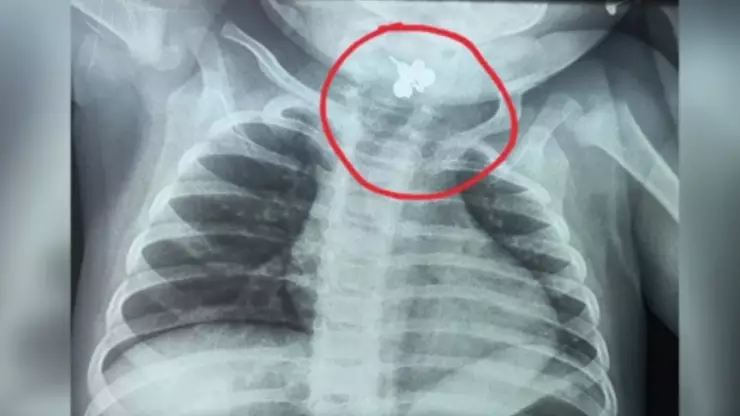

Gracias a una radiografía de tórax, se pudo identificar un objeto extraño alojado en la región faringolaríngea de la bebé. Se trataba de un anillo, cuya ausencia no había sido notada por la madre, ya que probablemente se encontraba en el dormitorio donde la menor pasaba gran parte del tiempo.

Este hallazgo cambió por completo el diagnóstico, además de que se activó un protocolo de emergencia médica.